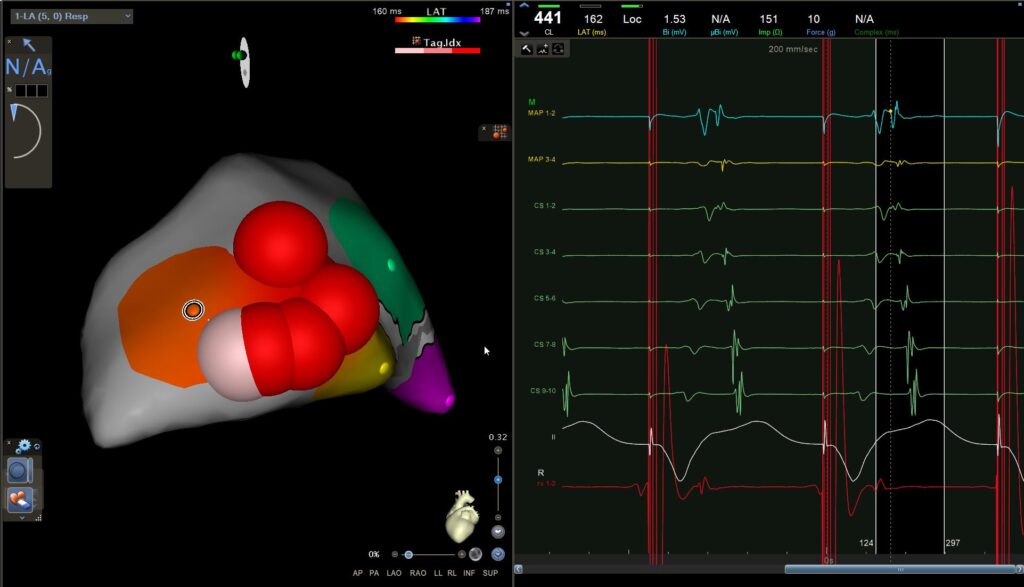

We can see that the best localisation is in the posterolateral region.

Here we are pacing at the ventricular level. We first see the activation of the CS progressing from CS1,2 toward CS9,10, and immediately after the application there is a change in activation, which becomes normal again, from CS9,10 toward CS1,2.